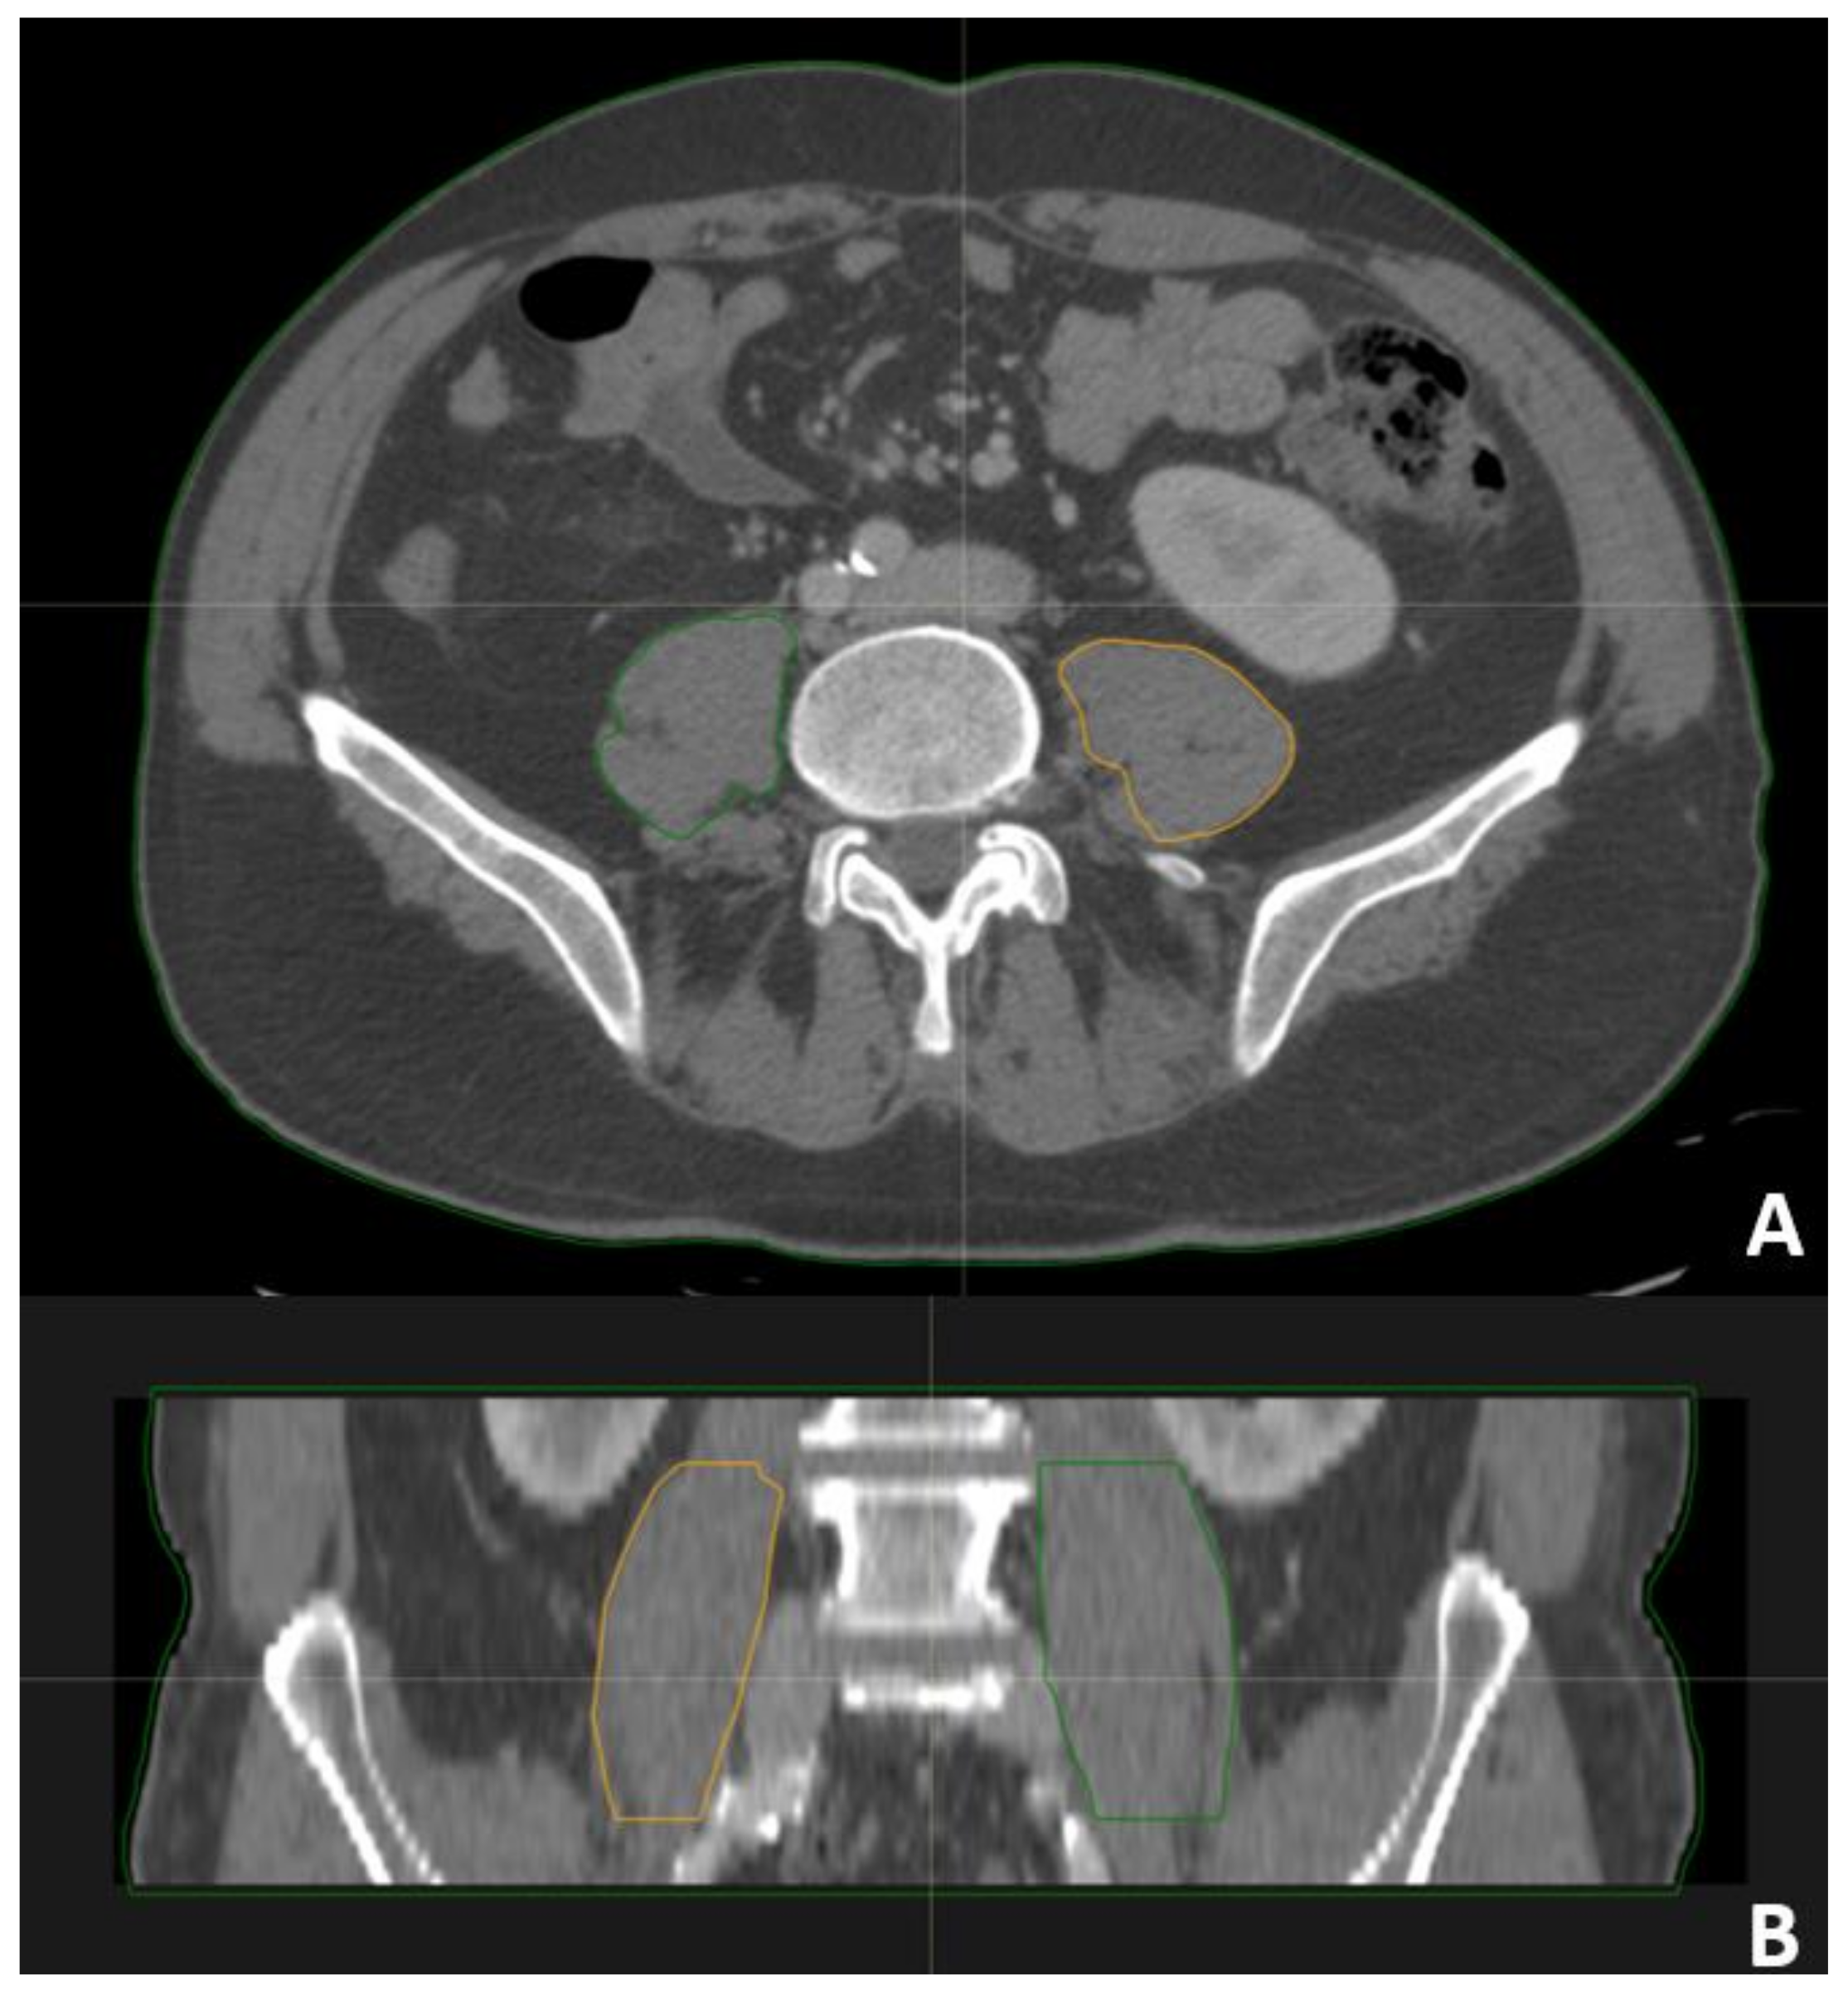

2.4. Psoas Contouring